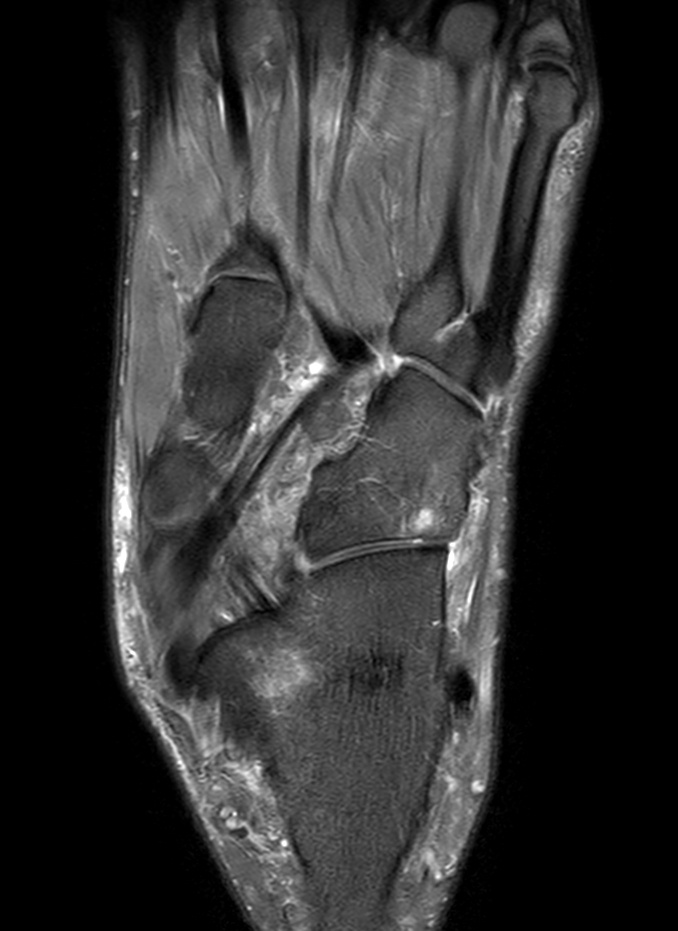

Coronal 3D PDw MSK VIEW